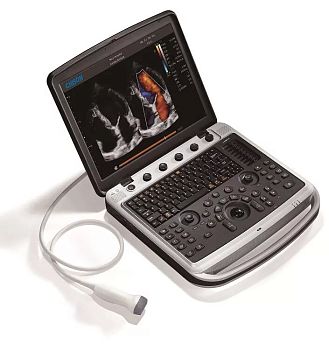

Портативный ультразвуковой аппарат Mindray DP-50

Mindray DP-50 - цифровая черно-белая ультразвуковая система портативного типа, оснащенная жидкокристаллическим широкоугольным монитором с диагональю 15 дюймов и возможностью изменения наклона для улучшения обзора и удобства врача. УЗИ сканер может работать от аккумулятора, а также от сети. Отличаясь компактными габаритами и имея сравнительно небольшой вес (всего 7,5 кг), легко размещается в помещениях с ограниченным пространством.

- qwerty-клавиатура с подсветкой и трекбол